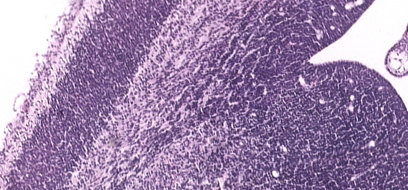

ELECTRONIC PRENATAL MOUSE BRAIN ATLASThe Electronic Prenatal Mouse Brain Atlas, EPMBA, at present consists of two sets of annotated images of coronal sections from Gestational Day (GD) 12 heads and GD 16 brains of C57BL/6J mice. Ten micron thick sections were stained with hematoxylin and eosin. Images were prepared at various resolutions for annotations and for high resolution presentation. A subset of sections were annotated and linked to anatomical terms. Additionally, horizontal sections of a GD 12 head were aligned and re-assembled into a 3D volume for digital sectioning in arbitrarily oblique planes. | ||